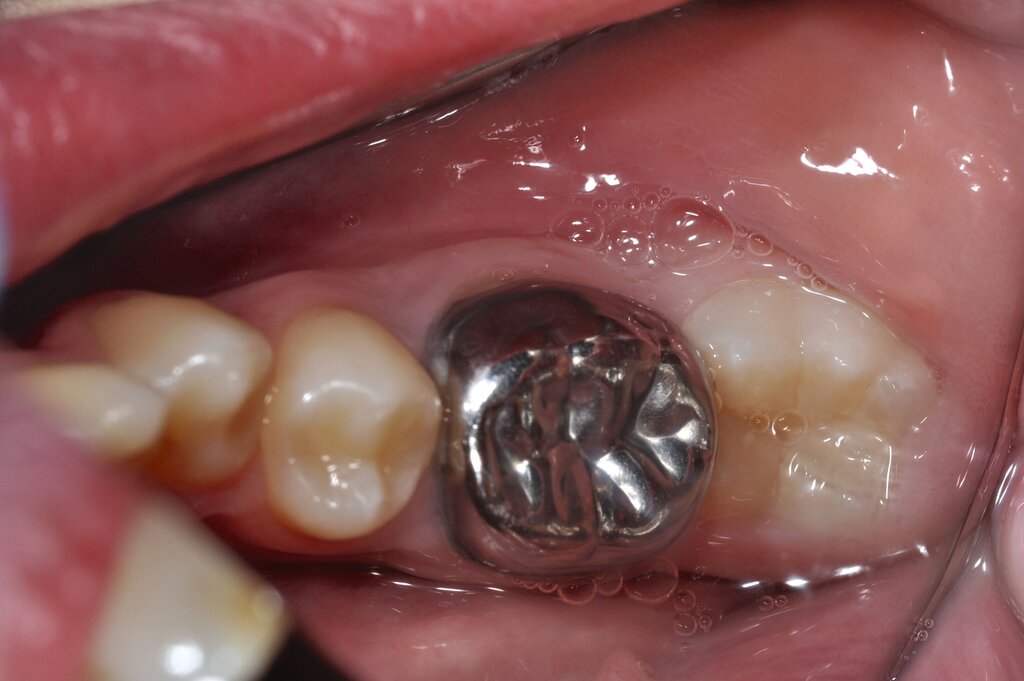

Die „temporäre Therapie“ umfasst neben den konfektionierten Edelstahlkronen (Abbildung 6) [Kotsanos et al., 2005; Oh et al., 2020] nun auch die vorgefertigten Zirkonoxidkronen [Geduk et al., 2023; Talekar et al., 2023]. Stahlkronen (SSC, stainless steel crowns; PMC, preformed metal crowns) werden heute auch mittels Halltechnik eingesetzt [Grizzo et al., 2022].

Vorteil ist dabei, dass aufgrund der geringen Schichtstärke der Kronen keine Zahnhartsubstanz geopfert werden muss. Die Indikation zum Einsatz dieses Verfahrens ist eine mittelfristige Versorgung über wenige Jahre, wenn beispielsweise der optimale Zeitpunkt für die Extraktion abgewartet werden muss. De Farias et al. konnten zeigen, dass über einen Zeitraum von 24 Monaten eine Versorgung von MIH-Molaren mit Stahlkronen eine signifikant höhere Überlebensrate aufwies als die Kompositversorgung [de Farias et al., 2022].